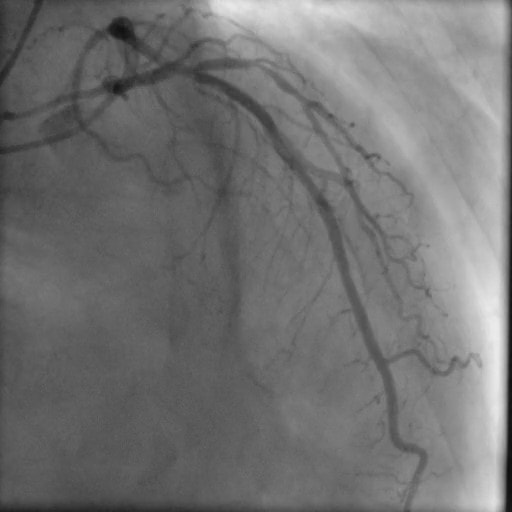

PCI前